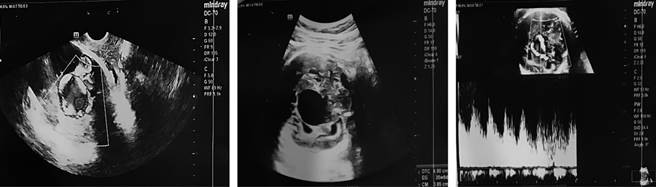

RN masculino, primer producto de una madre de 19 años. A las 25 semanas de gestación (SDG), por ecografía gestacional, se identificó un hematoma supratentorial. Mientras que a las 33.6 SDG, por sospecha de holoprosencefalia se realizó una neurosonografía fetal, en la cual se encontró imagen anecoica en forma de reloj de arena, de dimensiones de 74 × 37 mm, vascularizada, sugestiva de malformación venosa tipo aneurisma de la vena de Galeno (Figura 1). A las 35 SDG por ecocardiografía se detectó cardiomegalia con sobrecarga de cavidades derechas.

Figura 1: Neurosonografía fetal, 34.6 semanas de edad gestacional. En línea media se aprecia imagen anecoica en forma de reloj de arena de 74 × 37 mm, que abarca desde la región subtalámica hasta la región infratentorial y hasta el occipital, con flujo venoso en su interior, sugestivo de malformación arteriovenosa, con sospecha de aneurisma de la vena de Galeno.